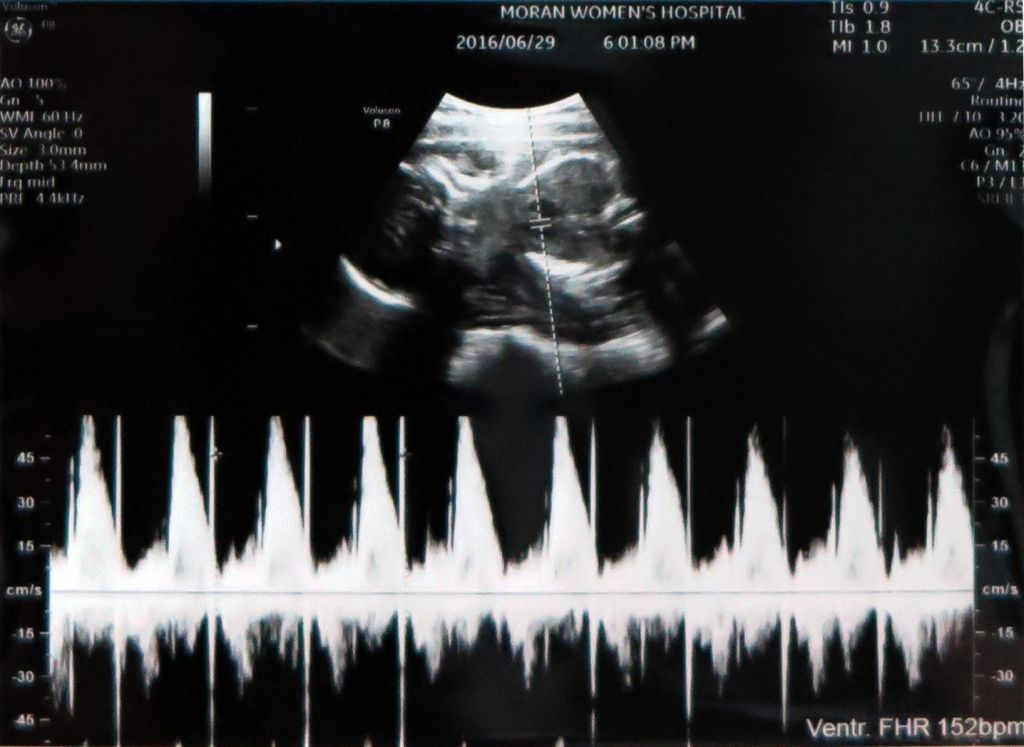

2016_06_29_1

앙증맞은 발을 찍어주신건 센스~★